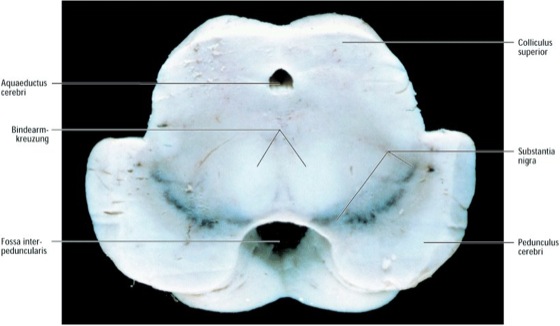

Synonyms for Substantia niagra in Free Thesaurus Antonyms for Substantia niagra 2 synonyms for substantia nigra locus niger, nucleus niger What are synonyms for Substantia niagra?. Axial section of the brain at the level of the midbrain, mamillary bodies Note that the substantia nigra separates the cerebral crus from the tegmentum of the midbrain. Facebook is showing information to help you better understand the purpose of a Page See actions taken by the people who manage and post content.

The spatiotemporal progression of neuronal loss related to disease duration can thus be drawn in the substantia nigra pars compacta for each Parkinson's disease patient depletion begins in the main pocket (nigrosome 1) and then spreads to other nigrosomes and the matrix along rostral, medial and dorsal axes of progression. Definition of substantia nigra a layer of deeply pigmented gray matter situated in the midbrain and containing the cell bodies of a tract of dopamineproducing nerve cells whose secretion tends to be deficient in Parkinson's disease Examples of substantia nigra in a Sentence. Substantia nigra The substantia nigra is one of the brainstem nuclei and part of the extrapyramidal system While other nuclei such as the red nucleus are as small and contained within an axial slice at the superior colliculi (see figure), the substantia nigra is seen in axial slices at both superior and inferior colliculi.

Substantia nigra is a part of midbrain, the top most structure present in the brain stem It is present in the anterior part of midbrain in the cerebellar peduncles Substantia nigra divides the cerebellar peduncles into anterior crus cerebri and posterior tegmentum of mid brain Anatomically it is present in the midbrain However,. CONCLUSION Highfieldstrength MR microscopy yielded pronounced differences in substantia nigra and globus pallidus of PSP compared with control brains Histologic data also suggested that the predominant iron in PSP is hemosiderin, not ferritin Iron in the brain is a contrast enhancer and potential biomarker for PSP. Find link is a tool written by Edward Betts searching for Substantia nigra 146 found (371 total) alternate case substantia nigra Brodmann area 12 (199 words) exact match in snippet view article find links to article It is indirectly connected to the global palladius as well as the substantia nigra, due to efferents to the striatumGlutaminergic input is turned into.